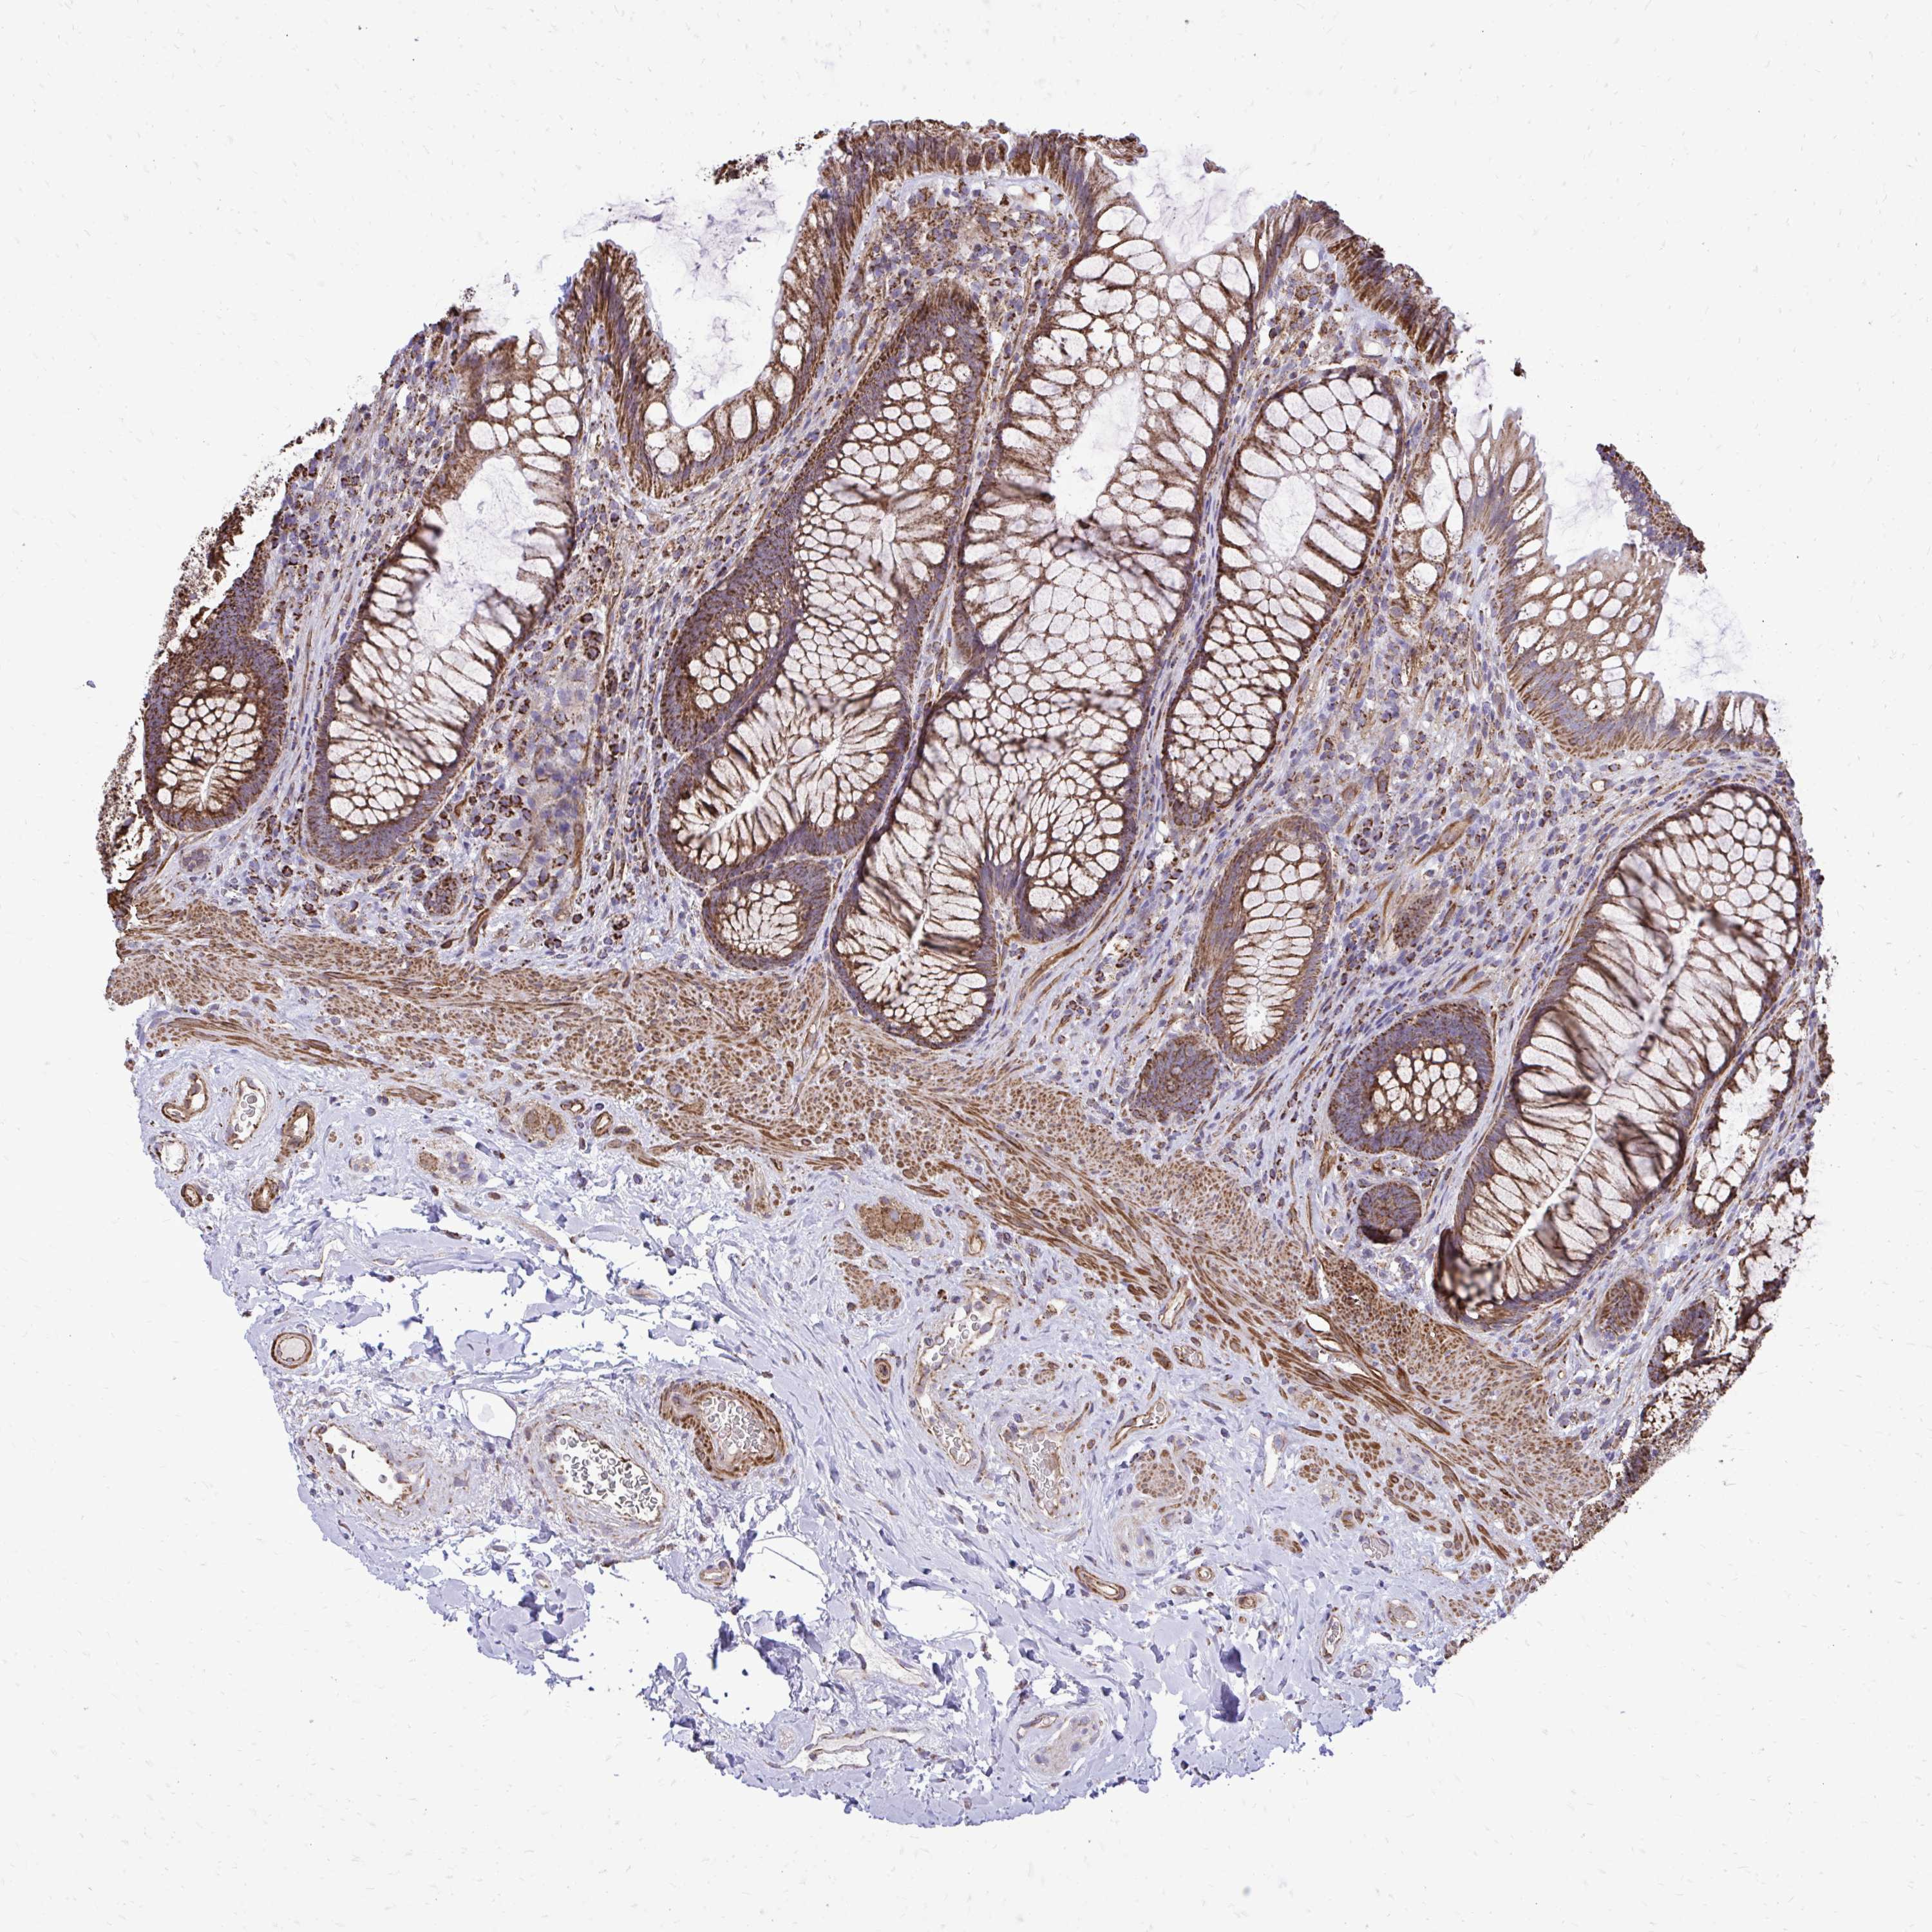

UBE2C